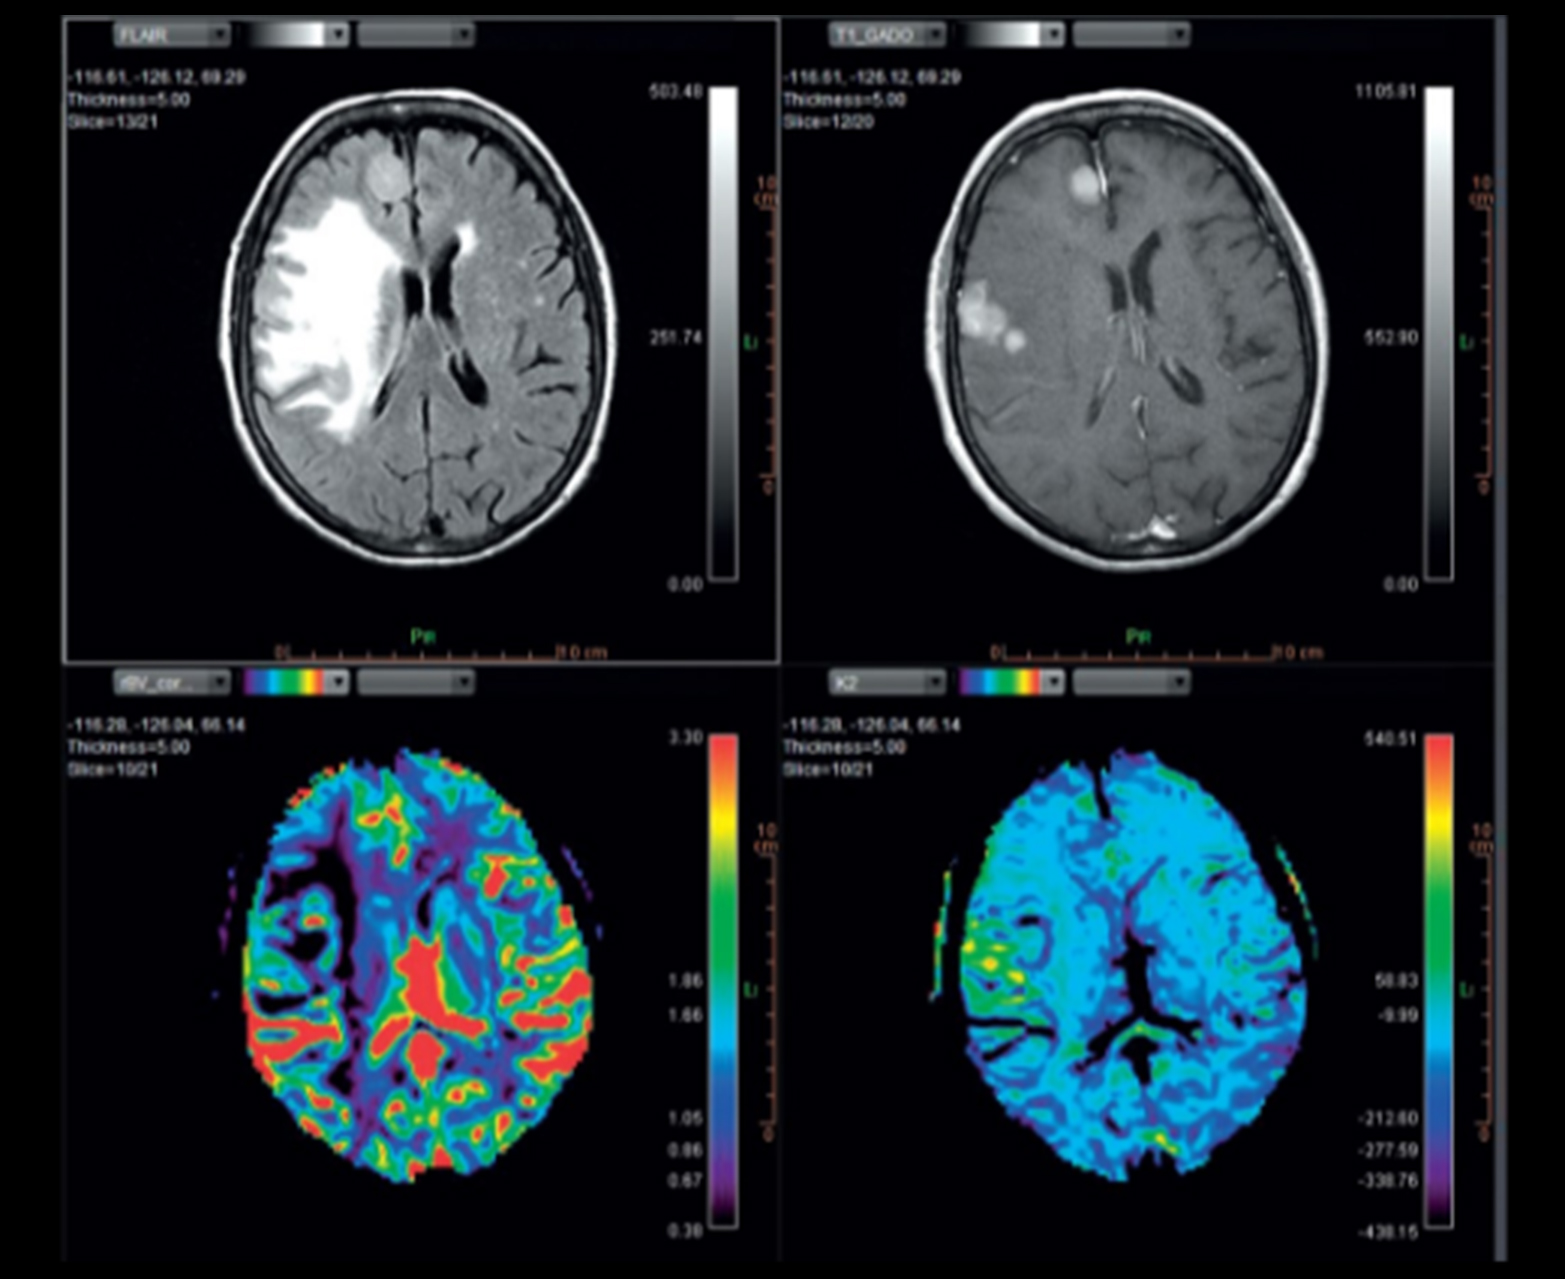

Автоматически и точно рассчитывает качественные и количественные карты проницаемости.

- Обнаружение, классификация и характеристика опухолей с быстрым доступом к качественной и количественной информации индивидуальный макет

Многопараметрическое настраиваемое отображение карт диффузии и перфузии, включая карты rCBV_corrected и K2